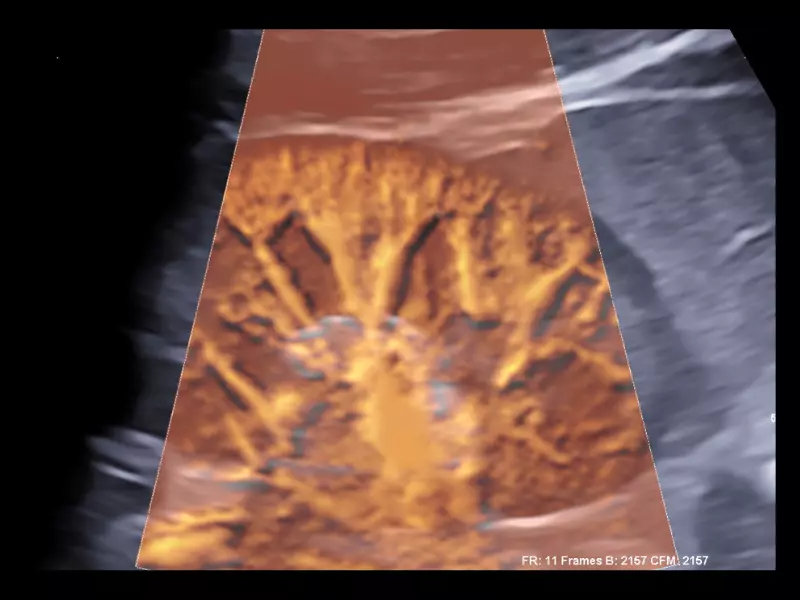

MyLab™9 Platform - Ultra-sensitivity Colour Doppler for precise visualization pulmonary veins

MyLab™9 Platform - Ultra-sensitivity Colour Doppler for precise visualization pulmonary veins